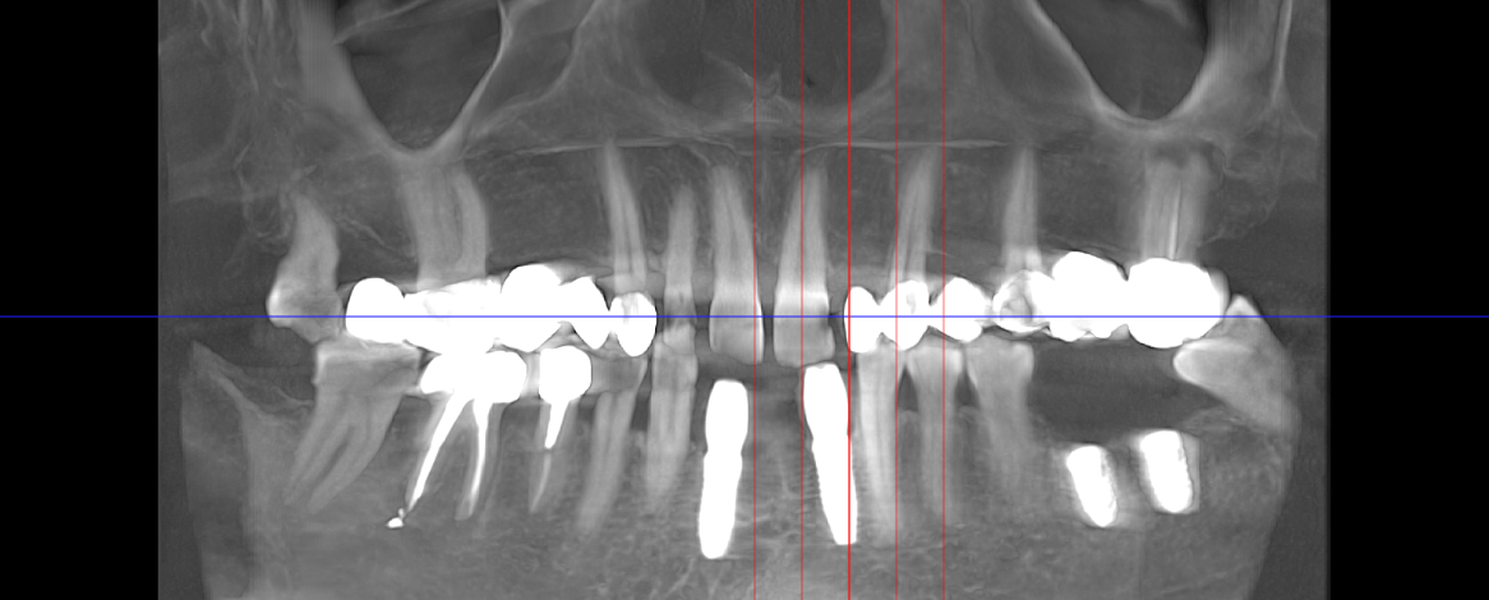

- Consultație, radiografie și plan de tratament personalizat